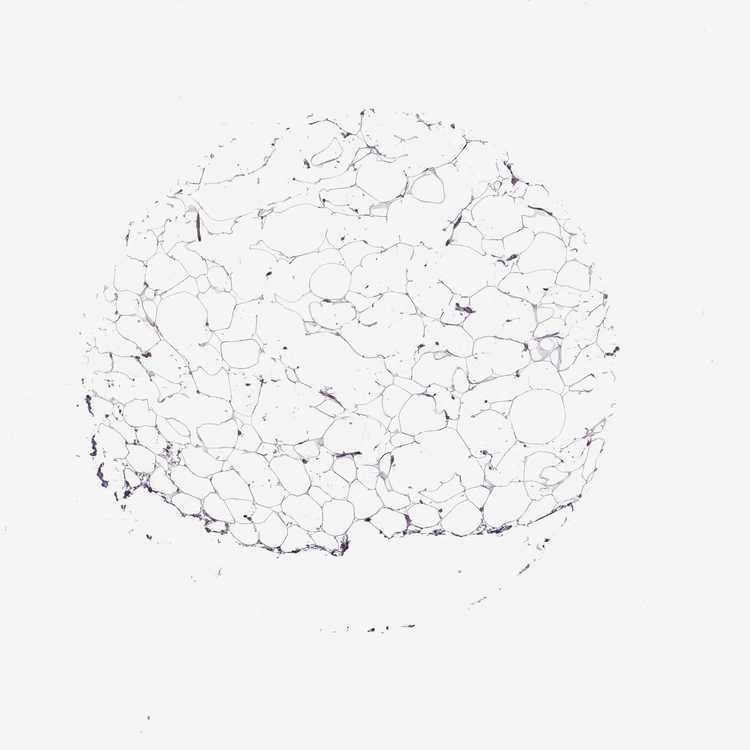

SOFT TISSUE 1 - Antibody stainingi

Antibody staining in the annotated cell types in the current human tissue is reported as not detected, low, medium, or high, based on conventional immunohistochemistry profiling in selected tissues. This score is based on the combination of the staining intensity and fraction of stained cells.

Each image is clickable and will lead to virtual microscopy that enables deeper exploration of all samples and also displays staining intensity scores, fraction scores and subcellular localization as well as patient and tissue information for each sample.

Antibody HPA065718Antibody HPA068266

Chondrocytes -Not detected

Fibroblasts Not detectedNot detected

Peripheral nerve -Not detected